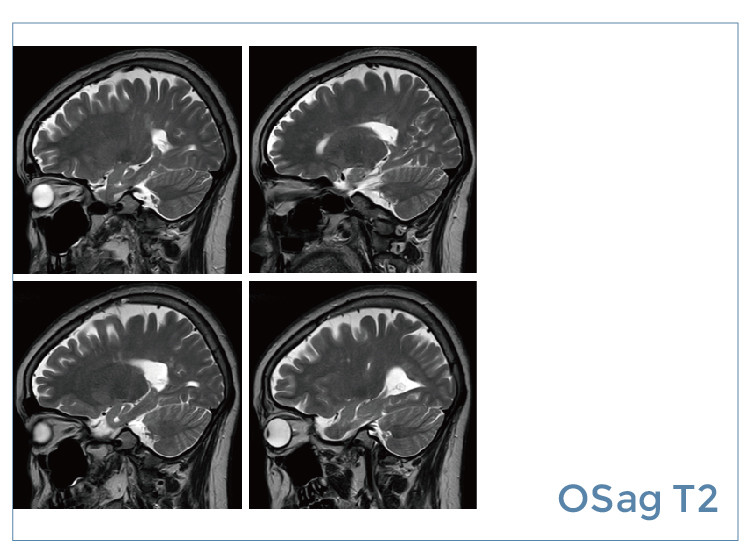

【朗润影像档案】20190823磁共振影像病例结果讨论